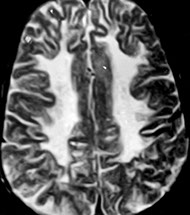

Multiple sclerosis (MS)

Chronic demyelinating dz of CNS in 1/1000 US citizens, F>M, ~30 yo

- inflammatory demyelinating dz c multiple, randomly disseminated demyelinated lesions "plaques", as well as by chronic inflammation (lesions separated by space and time); dz active despite clinical remission

- lesions of MS are multiple, asymmetric, randomly distributed foci (plaques) of primary demyelination, (i.e., with relative preservation of axons). Dz most prominent in white matter of brain stem, spinal cord, optic nerves, cerebrum, and cerebellum. Periventricular plaques are quite common.

Imaging: plaques in periventricular white matter are classic ("Dawson's fingers")

Gross: fresh, active plaques are round, edematous, bulging c ill-defined pink color; inactive "burnt-out" plaques are sunken, ell-defined, transprent, and better visualized than active plaques

- plaques seen in both grey and white matter (usually white)

Micro: Oligodendrocytic dropout and reactive gliosis in periventricular areas, although the axons are preserved

- areas of demyelination known as plaques, and can be found in cerebral white matter, spinal cord or brain stem

-- active (acute) plaques have dense lymphs and macrophages around vessels and in parenchyma, with swollen edematous axons

- chronic inactive plaques are densely gliotic c los of oligos and myelin and MC thin, naked axons, c little or no inflam

- periventricular white matter pallor can be highlighted c LFB

Multiple sclerosis

Multiple sclerosis - larger MS plaques are outlined in red and would be firm to the touch (the sclerotic part of MS)